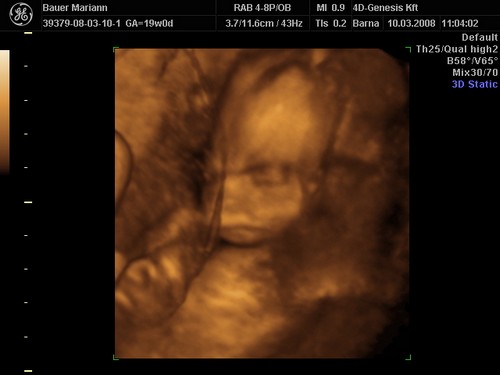

A doki szerint pufók kislány